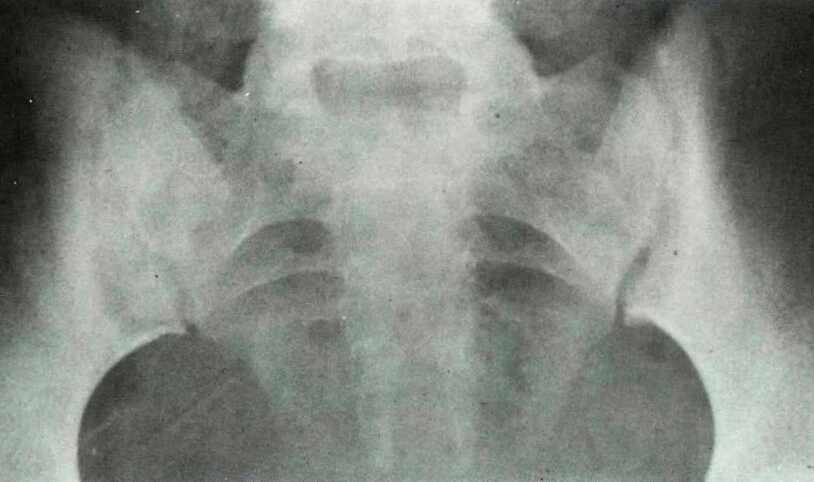

What is the radiographic feature? What disease is this associated with?

subperiosteal resorption at SI joints

HPT